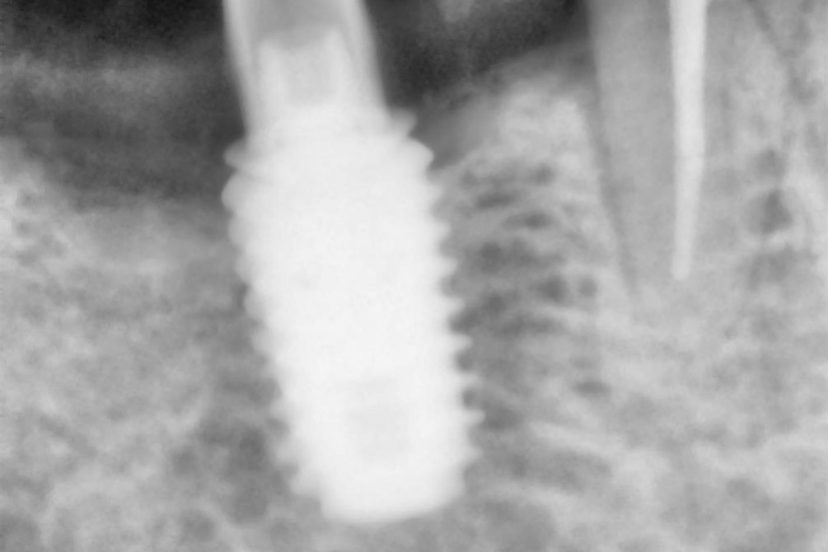

Successful implant treatment depends on the ability to act like natural teeth and be in harmony with the tissue and the bone. Basic precautions can be important for that and advanced level techniques must be performed by the clinician, and the implant must include the technology to imitate natural structure.

a- The clinician must have some surgical knowledge and experience as positioning the implant, and needs to avoid trauma.

b- If possible implant must be implanted right after the extraction of the tooth. Scientifically proved that bone in the extraction area melts 30% to 60% in the next 6 months. This causes the bone melting and gum retraction in the implant area.

d- If implanting after the extraction is not possible, the cavity must be filled with special material and technique for protection against bone melting.